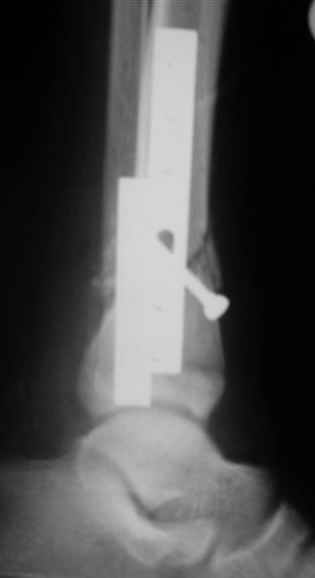

АВФ -отдельная история в нашем краю, поэтому последний вариант -открытая репозиция, что я и сделал: Без мобилизации отломков б.б. репозиция м.б. не получалась. Первым делом фиксировал перелом м.б. кости пластиной на 4 4,5 мм винтах,

при ревизии зоны перелома б.б. кости сохранялось смещение дистального отломка кпереди, пришлось принять меры и решить эту проблему.

Послеоперационные снимки сегодня посмотрел - все выглядит вполне анатомично, кроме длины

винтов на м.б. кость - слегка переборщил:-(( Не было камеры с собой , но как только

пересниму картинки обязательно вышлю.

Помятуя наш недавний разговор о фиксации м.б. кост, высылаю послеоперационные картинки..

Напомню- разбирали случай 17 летнего молодого человека перелом дист тиб.фиб. хирургия после 3 недель с момента травмы( безуспешные попытки закрытой репозиции) Раны заживают первичным натяжением, занимается физиотерапией, пока никаких проблем не наблюдается